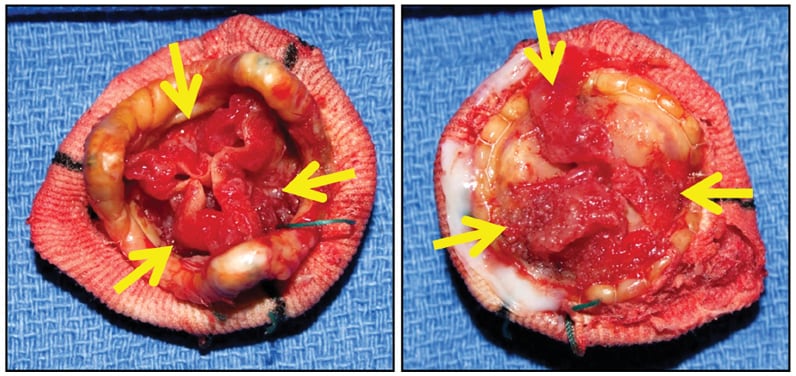

St. Jude porcine bioprosthesis

St. Jude porcine bioprosthesis

St. Jude porcine bioprosthesis, with degenerating old obstructive thrombus (arrows) along both sides of all three cusps (left, downstream side; right, upstream side). There was no acute inflammation or identifiable microorganisms.